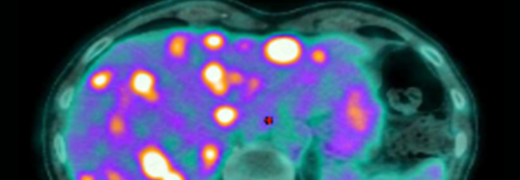

Une avancée majeure dans le traitement du cancer anal grâce à une stratégie combinant immunothérapie et radiothérapie adaptative

L’équipe de cancérologie digestive du CHU de Besançon / IRFC Franche-Comté vient de publier dans The Lancet Oncology une étude majeure qui pourrait transformer la prise en charge du carcinome épidermoïde...